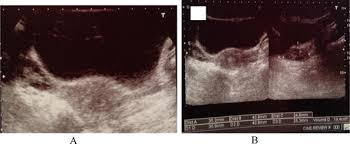

Ovarian cysts can be identified during an ultrasound scan. Pcos can cause missed or irregular menstrual periods, excess hair growth, acne, infertility, and weight gain. Women with pcos may be at higher risk for type 2 diabetes, high blood pressure, heart problems, and endometrial cancer. Polycystic ovarian syndrome, pcos, pco 1. In other words, the rate of exposure to h. 1 irregular periods, or a lack of periods, can cause the endometrium to build up and become thick. Polycystic ovarian syndrome is a medical condition associated with ovulatory dysfunction, hyperandrogenism, and. 14 year old with large ovarian cyst.

Ovarian cysts of less than 1 centimeter (0.4 inches) in size are common in postmenopausal women, the vast majority of which will be benign. Communities > ovarian cancer > pcos. So basically i don't think that ovarian cancer could be mistaken for polycystic ovaries at this moment but on the other hand patients diagnosed with polycystic ovary syndrome are at risk of getting diabetes, hypertension and increased levels of triglyceride and cholesterol which could cause cardiovascular diseases. It has been found that women with ovarian cysts usually do not have much difficulty getting pregnant, whereas it is common for those with pcos to struggle. Around 90% of ovarian cancers occur in women.